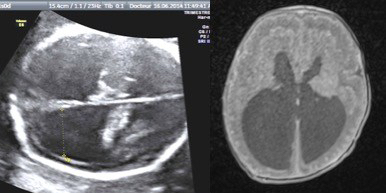

l’hydrocéphalie peut souvent être diagnostiquée à l’échographie anténatale car le liquide ventriculaire est particulièrement trans-sonique ; les mesures répétées de la taille ventriculaire permettent de juger de l’évolutivité. le pronostic dépend de la cause et de l’évolutivité.

le diagnostic

il est fait sur une augmentation de taille du carrefour ventriculaire ou atrium, qui est normalement inférieur à 10 mm, et qui reste à peu près stable au cours de la grossesse. on parle d’hydrocéphalie quand la taille ventriculaire atteint 12 mm. la progression en taille d’une échographie à l’autre est un élément majeur de pronostic.

le périmètre crânien est généralement augmenté, et il augmente au delà des valeurs normales au cours de la grossesse ; si le PC reste normal il faut envisager une ventriculomégalie de cause médicale.